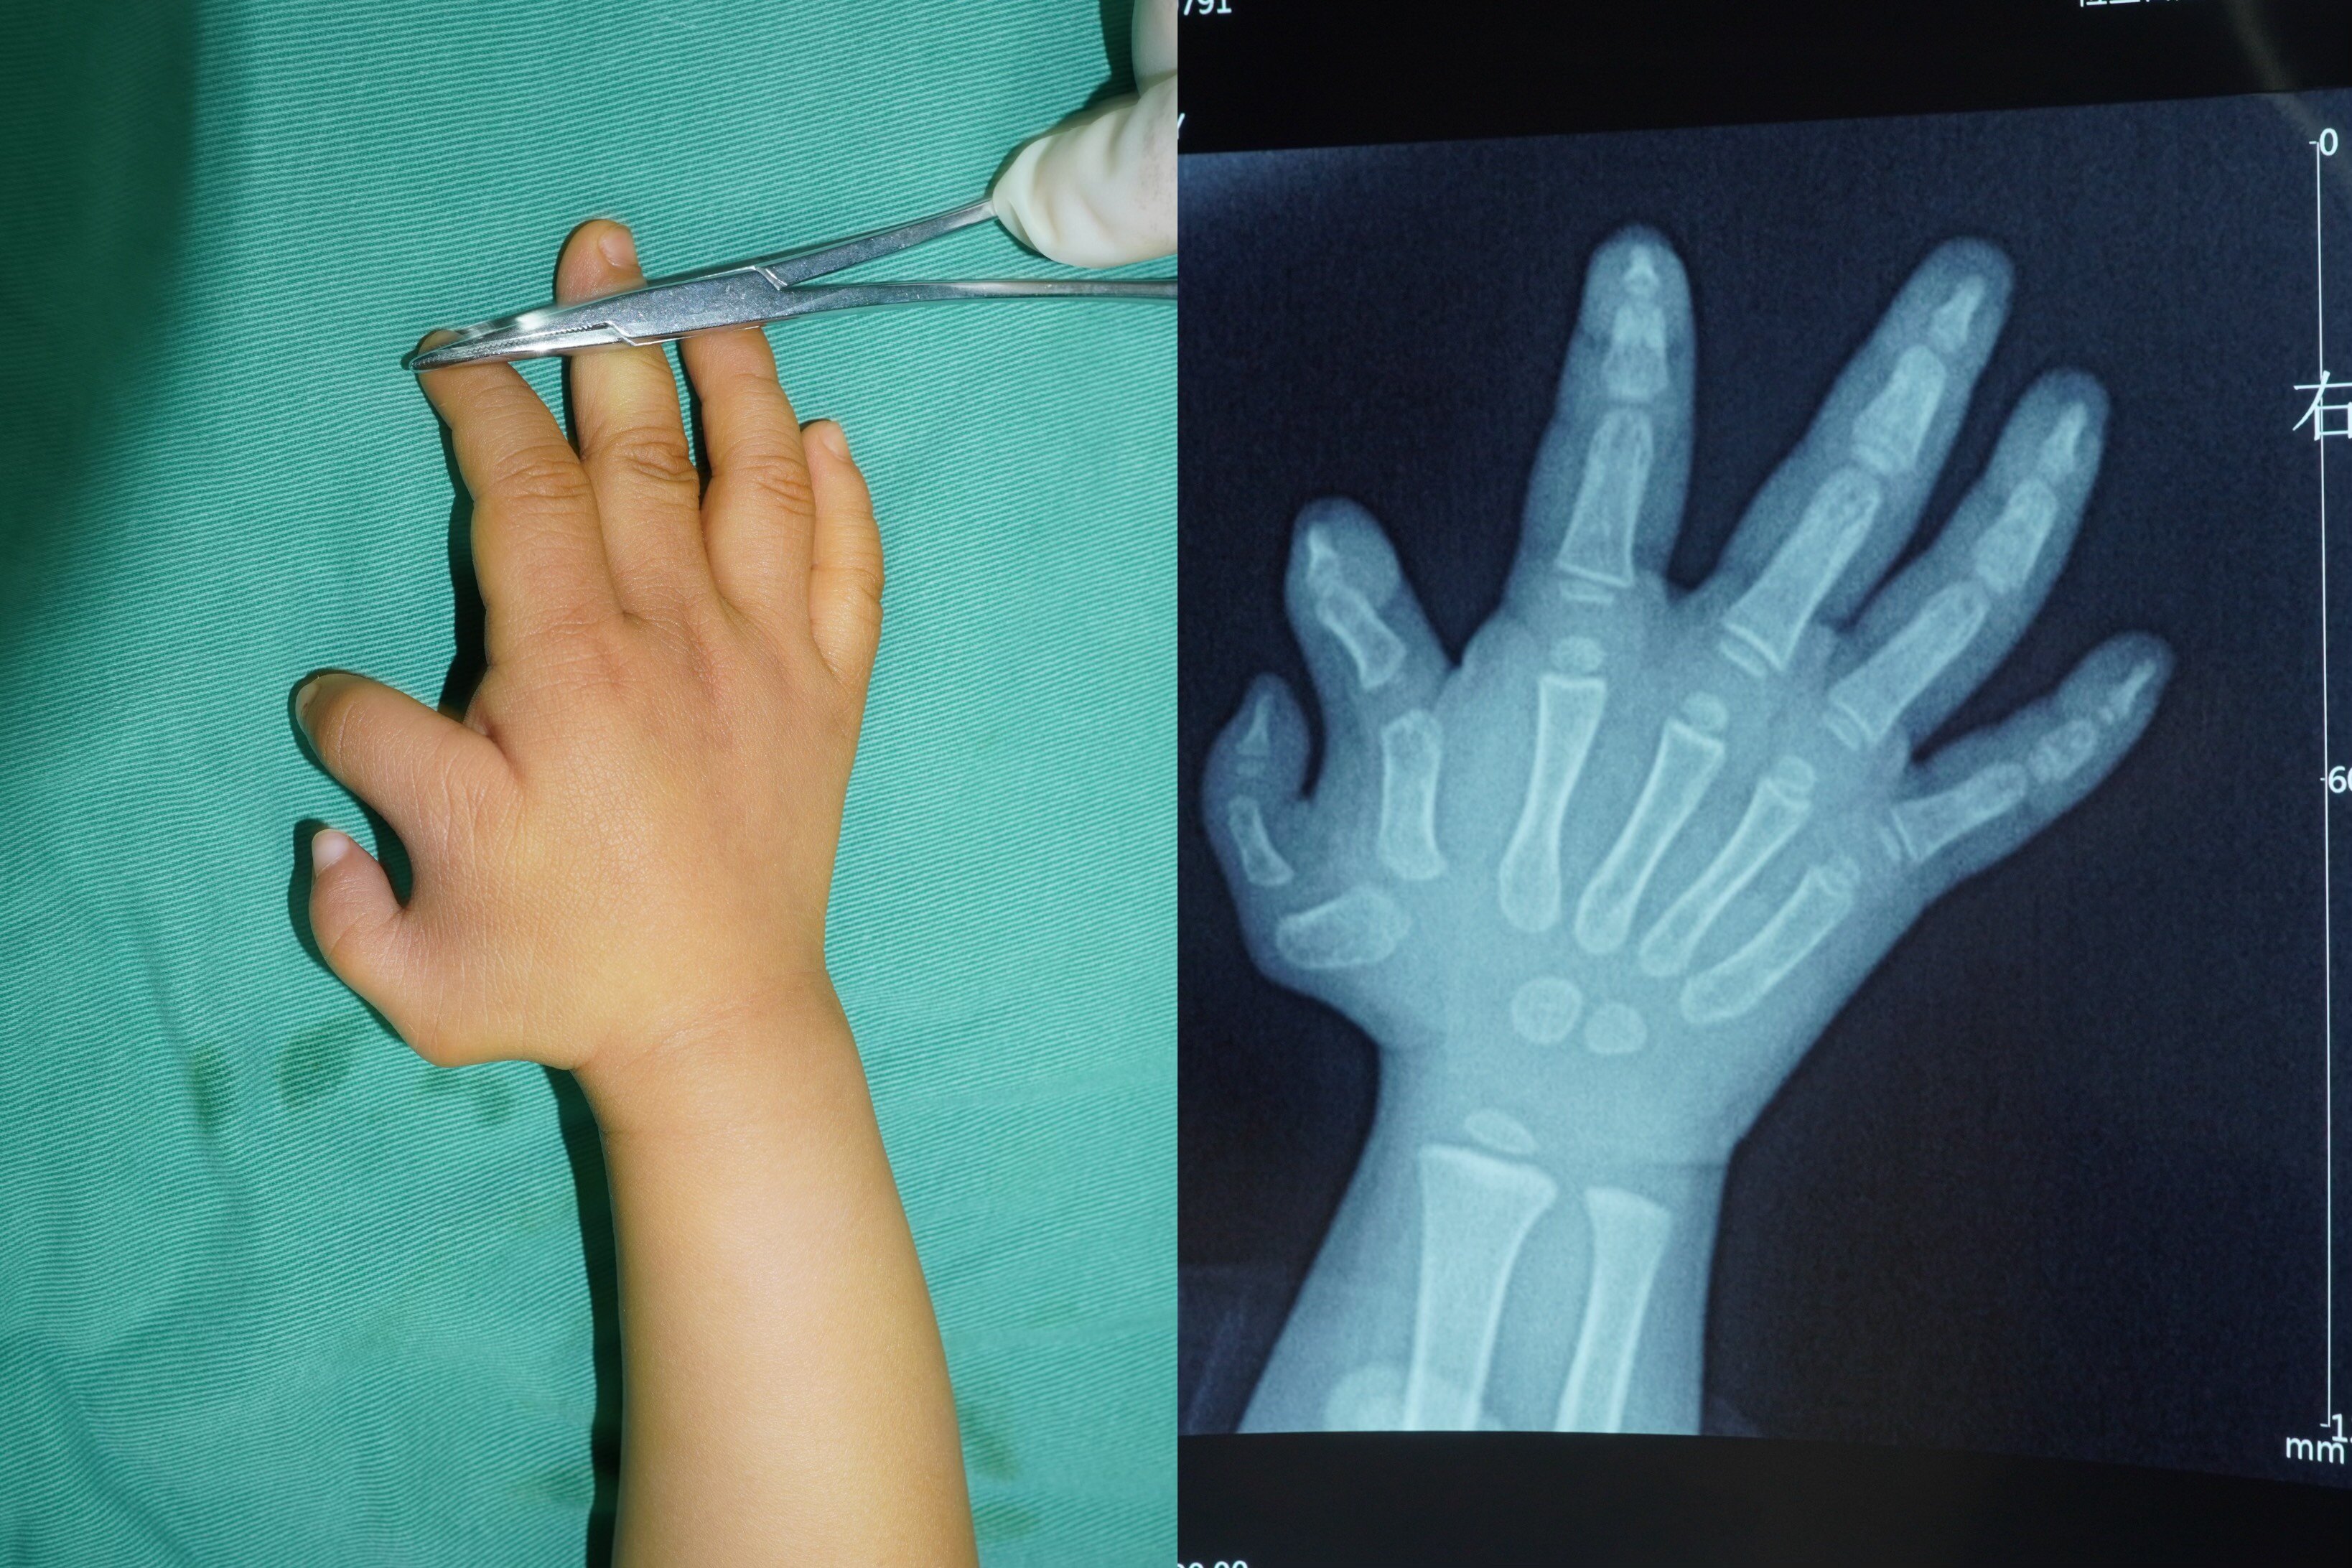

多指的分類,目前多采用Wassel分類法,共分為7型,I型:末節(jié)指骨分叉型II型:末節(jié)指骨復(fù)指型III型:近節(jié)指骨分叉型IV型:近節(jié)指骨復(fù)指型V型:掌骨分叉型VI型:掌骨復(fù)指型VII型:三節(jié)指骨型,伴其中一指為三節(jié)指骨型下面通過一些手術(shù)前后的情況,家長可以更加直觀的看到恢復(fù)情況。I型多指:II型多指:III型多指:IV型多指:V型多指:VI型多指:VII型多指: